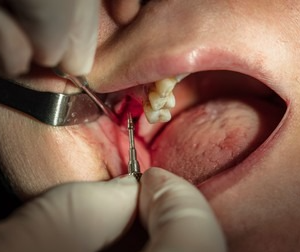

Scaling and Root Planing (Deep Cleaning)

Clears plaque and tartar from above and beneath the gum line, stopping infection from spreading.